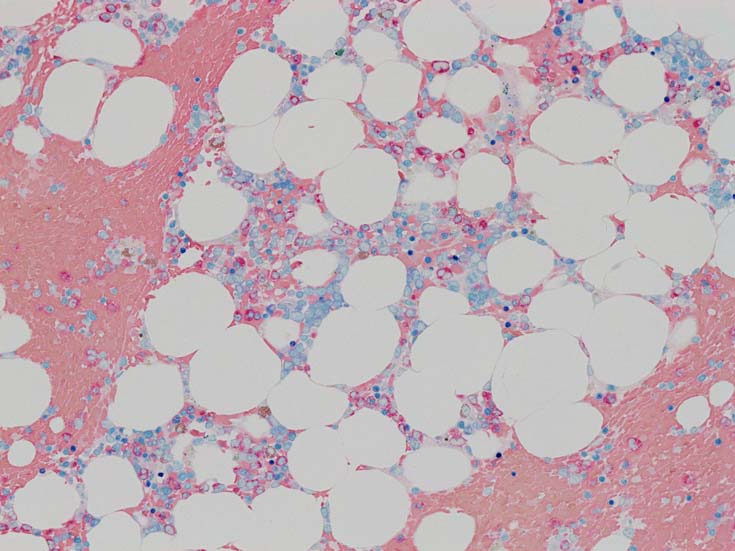

MDS症例のHbF発現.

サムネイル画像をクリックすると大きな画像が見られます.

MDSでの赤芽球HbF発現は, 陽性細胞はそれほど多くない印象ですが, この低形成性MDS症例では, 多くの陽性細胞がaggregatesを形成していました.